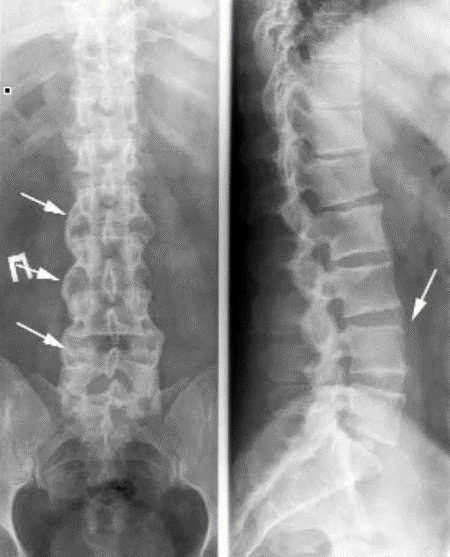

Спондилит - воспаление структур осевого скелета. Проявляется воспалительной болью в спине (ВБС), которая оценивается по критериям ASAS (2009).

Аксиальное поражение при ПсА имеет ряд особенностей. В 25% случаев сакроилиит и спондилит при ПсА протекают латентно (без боли). Сакроилиит при ПсА, в отличие от АС, – часто асимметричный. Для ПсА характерно медленное рентгенологическое прогрессирование сакроилиита, полный анкилоз КПС на фоне длительного течения заболевания отмечается значительно реже, чем при АС (до 6% пациентов). При ПсА возможно поражение позвоночника (рентгенологические признаки спондилита) без сакроилиита, чего не наблюдается при анкилозирующем спондилите (АС). При ПсА, в противоположность АС, синдесмофиты чаще малочисленны, расположены асимметрично, в случайном порядке, не вдоль ≪последовательно идущих≫ позвонков, имеют больший размер и объемную форму, встречаются паравертебральные синдесмофиты (ПВС) – особый вариант обызвествления передней продольной связки позвоночника. ПВС представляют собой широкие грубые оссификаты, которые отстоят от края тела позвонка. Также наблюдаются краевые синдесмофиты (КС) – вертебральные оссификаты, отходящие от края тела позвонка вверх. КС могут образовывать ≪мостики≫ между позвонками. КС и ПВС ориентированы вверх (сужения смежного межпозвонкового промежутка не наблюдается). Это отличает их от выявляемых при дегенеративных заболеваниях позвоночника остеофитов (или спондилофитов), которые ориентированы горизонтально, около измененного диска (сужение межпозвонкового промежутка). Нередко, несмотря на существенные рентгенологические изменения, у больных отсутствуют заметные функциональные нарушения, что также отличает спондилит при ПсА от поражения позвоночника при АС. Спондилит и сакроилиит могут наблюдаться при любой клинической форме ПсА.

Рисунок 11. Рентгенограммы нижнегрудного и поясничного отделов позвоночника при псориатическом артрите. Спондилит, грубые синдесмофиты, уплотнение передней продольной связки (стрелки)

Рисунок 12. Рентгенограмма стоп при псориатическом артрите. Асимметричный эрозивный артрит с остеолизом ПлФС правой стопы и внесуставная эрозия 1-го межфалангового сустава